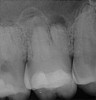

Fig 11. Preoperative radiograph. Courtesy of Dr. Guillaume Jouanny.

Figure 11

Fig 12. Postoperative radiography after full pulpotomy was performed. Courtesy of Dr. Guillaume Jouanny.

Figure 12

Fig 13. Tooth was asymptomatic at 1-year follow-up. Courtesy of Dr. Guillaume Jouanny.

Figure 13

Fig 14. Contralateral tooth at 1-year follow-up. Courtesy of Dr. Guillaume Jouanny.

Figure 14